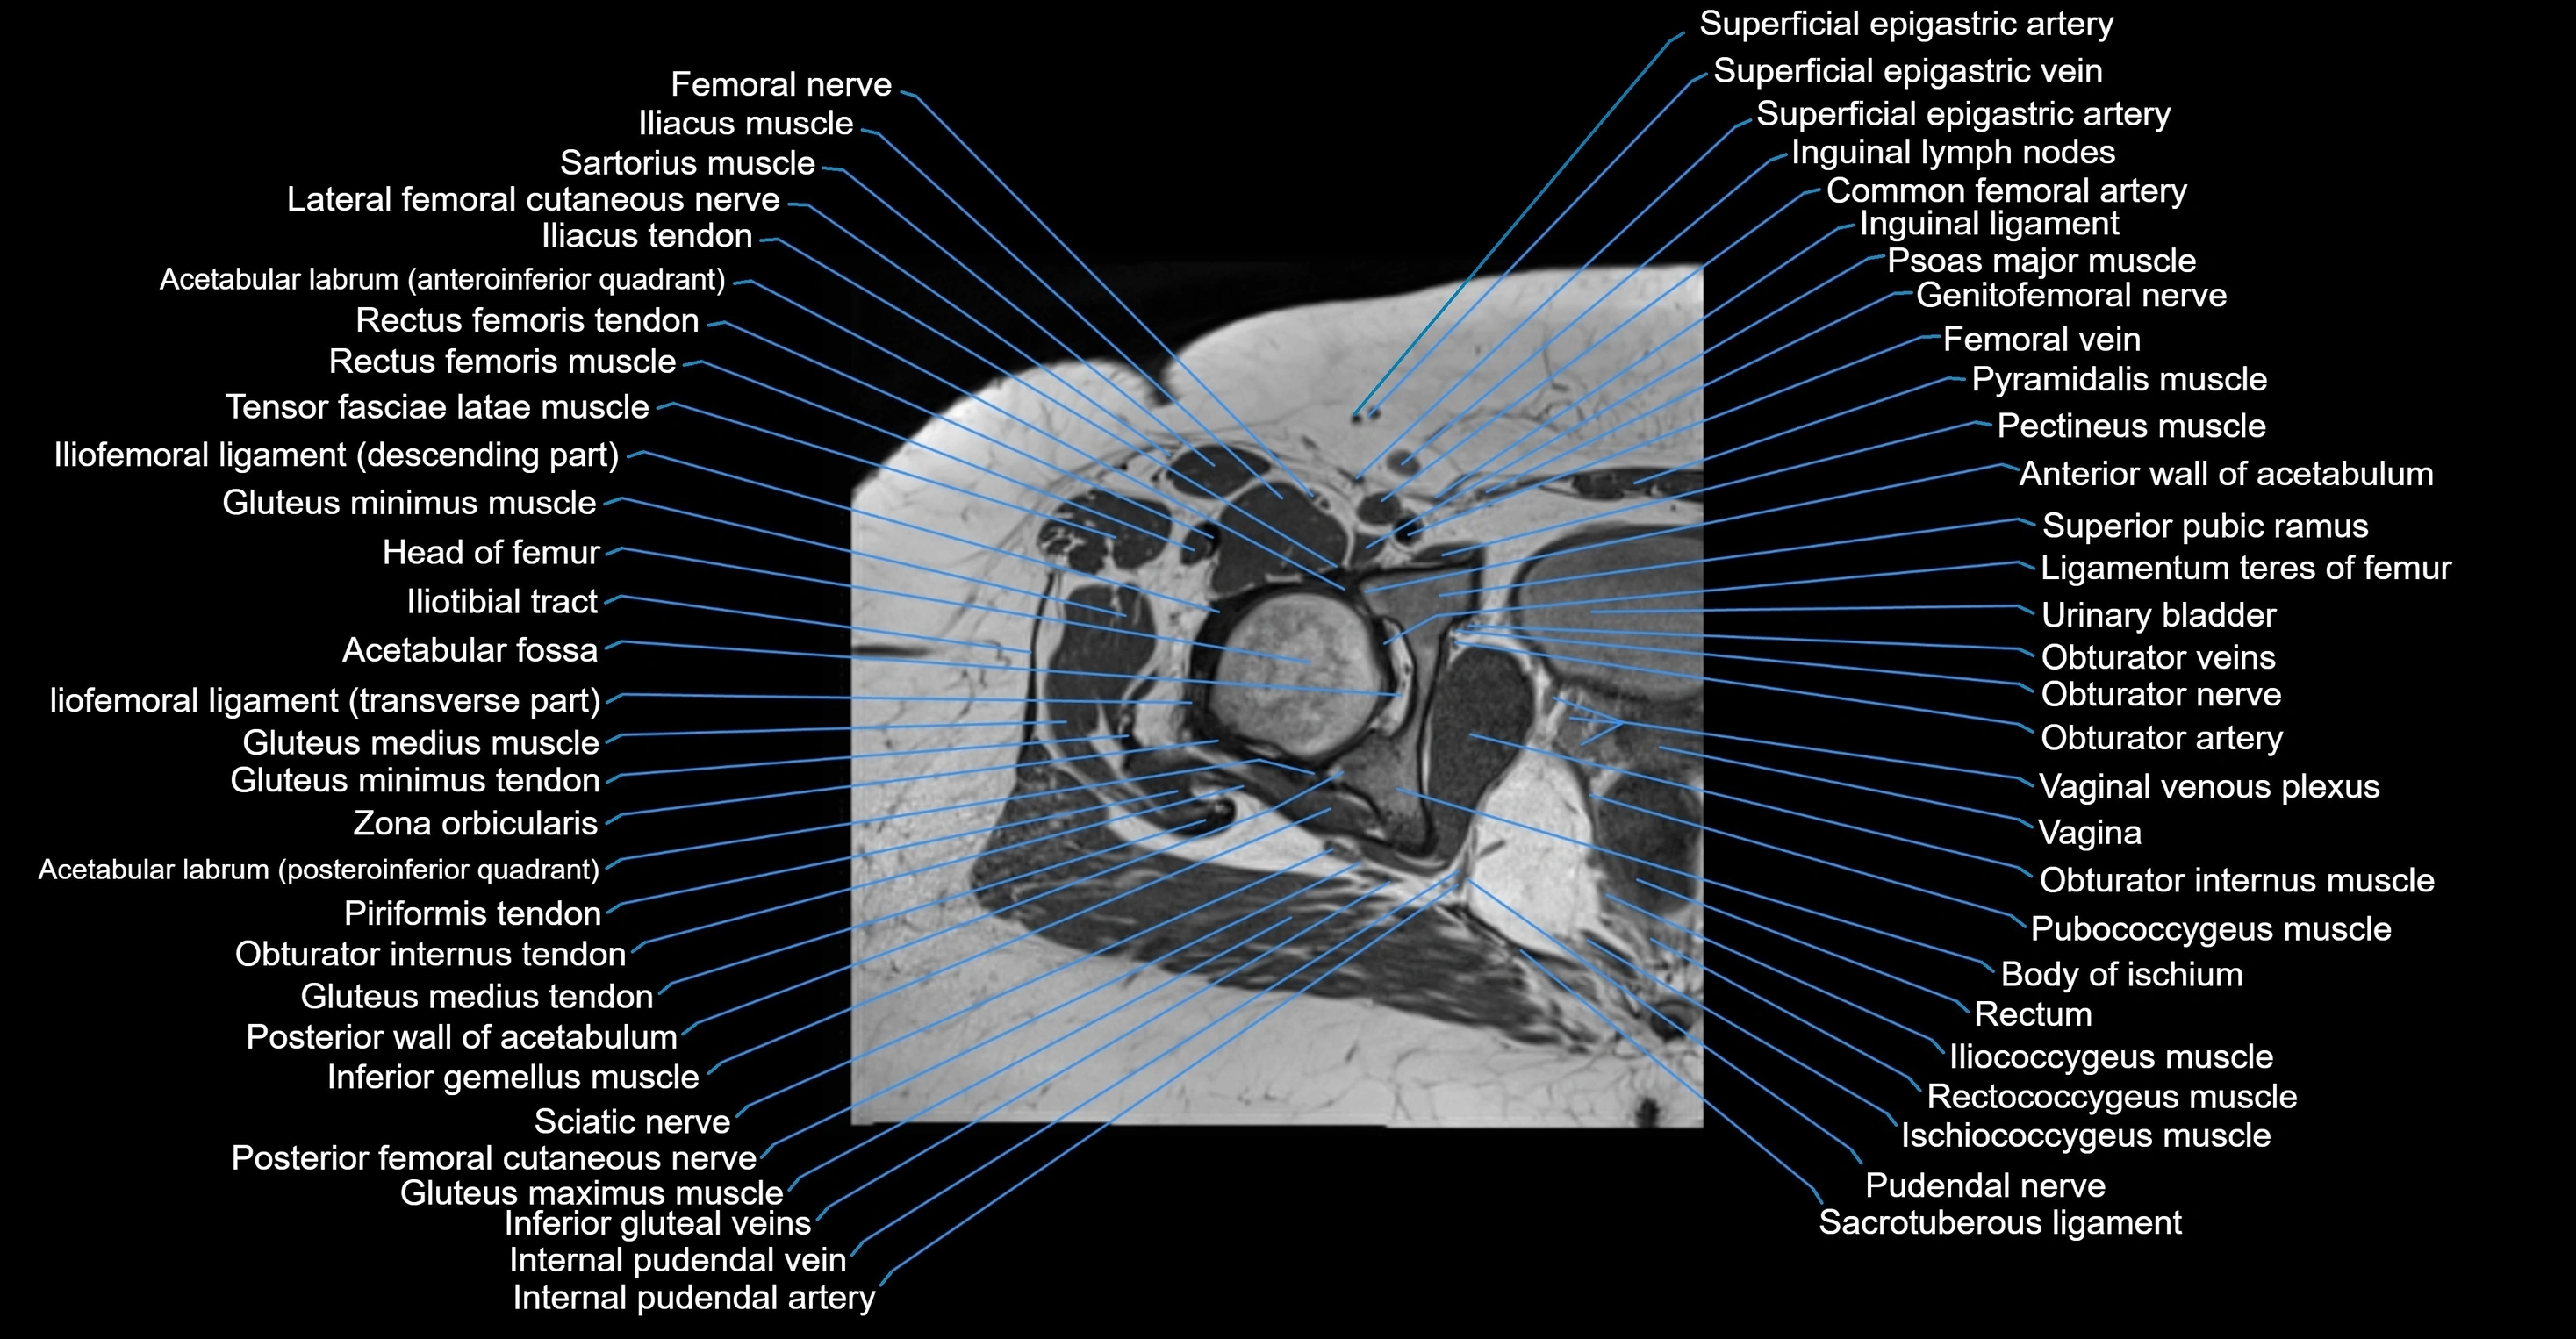

- Acetabulum

- Anterior wall of acetabulum

- Body of ischium

- Head of femur

- Hip joint

- Obturator internus muscle

- Obturator internus tendon

- Obturator nerve

- Obturator vein

- Obturator veins

- Pectineus muscle

- Pubococcygeus muscle

- Pudendal nerve

- Rectum

- Urinary bladder

- Vagina

- Vaginal venous plexus